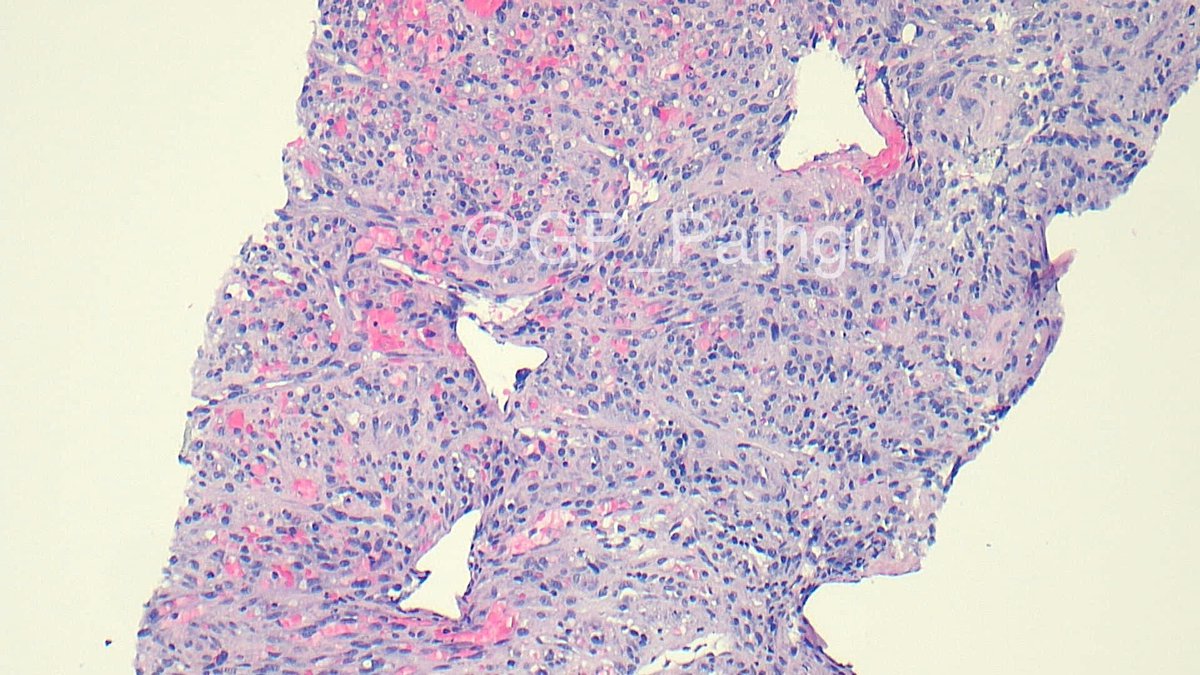

Schistosoma haematobium in a high-grade urothelial carcinoma resection. Weirdly present in the ureters and seminiferous tubules as well. Critters are among us. @UTHSC_ID @natesumMRSA